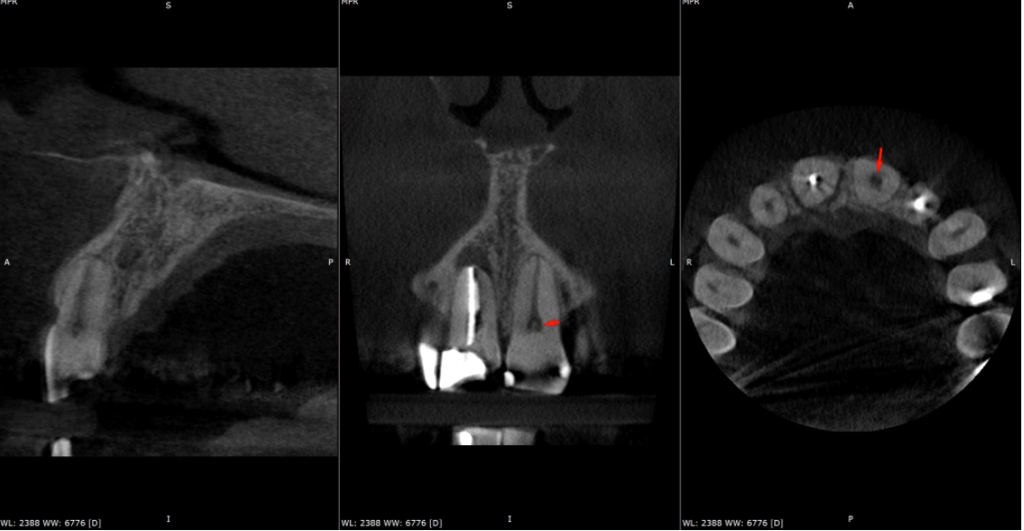

Pre-op IOPA and CBCT of the UR1 and UL2 looked like this:

Key findings from CBCT Consultant radiologist’s report by JM Radiology:

UR1

- Root filling under condensed.

- Large PARL (approx. 5mm) causing dehiscence of buccal cortex.

- Coronal one third of canal demonstrates some widening – likely to be anatomical rather than resorption and was mirrored on the UL1.

- No evidence of a fracture.

UL2

- Root filling a little under condensed.

- Large PARL; 6.5mm in diameter and dehiscence of the buccal cortex.